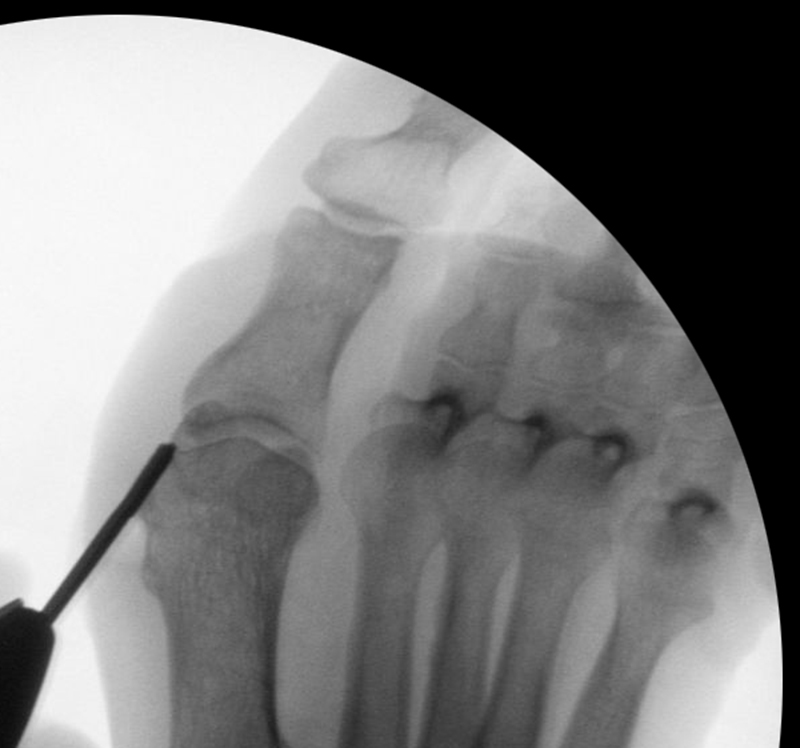

• Die Operationsplanung erfolgt anhand der Röntgenaufnahmen des Vorfußes unter Belastung in 2 Ebenen. Für die Verfahrenswahl sind wichtig der Intermetatarsalwinkel und die Breite des Os metatarsale, der Hallux valgus Winkel, der distalen Gelenkflächenwinkels (Distal Metatarsal Articular Angulation - DMAA), des Metatarsaleindex und Sesambeinposition (Abb. 1).

• Positionierung des Bildverstärkers im 90° Winkel zur Fußlängsachse (Abbildung 4).